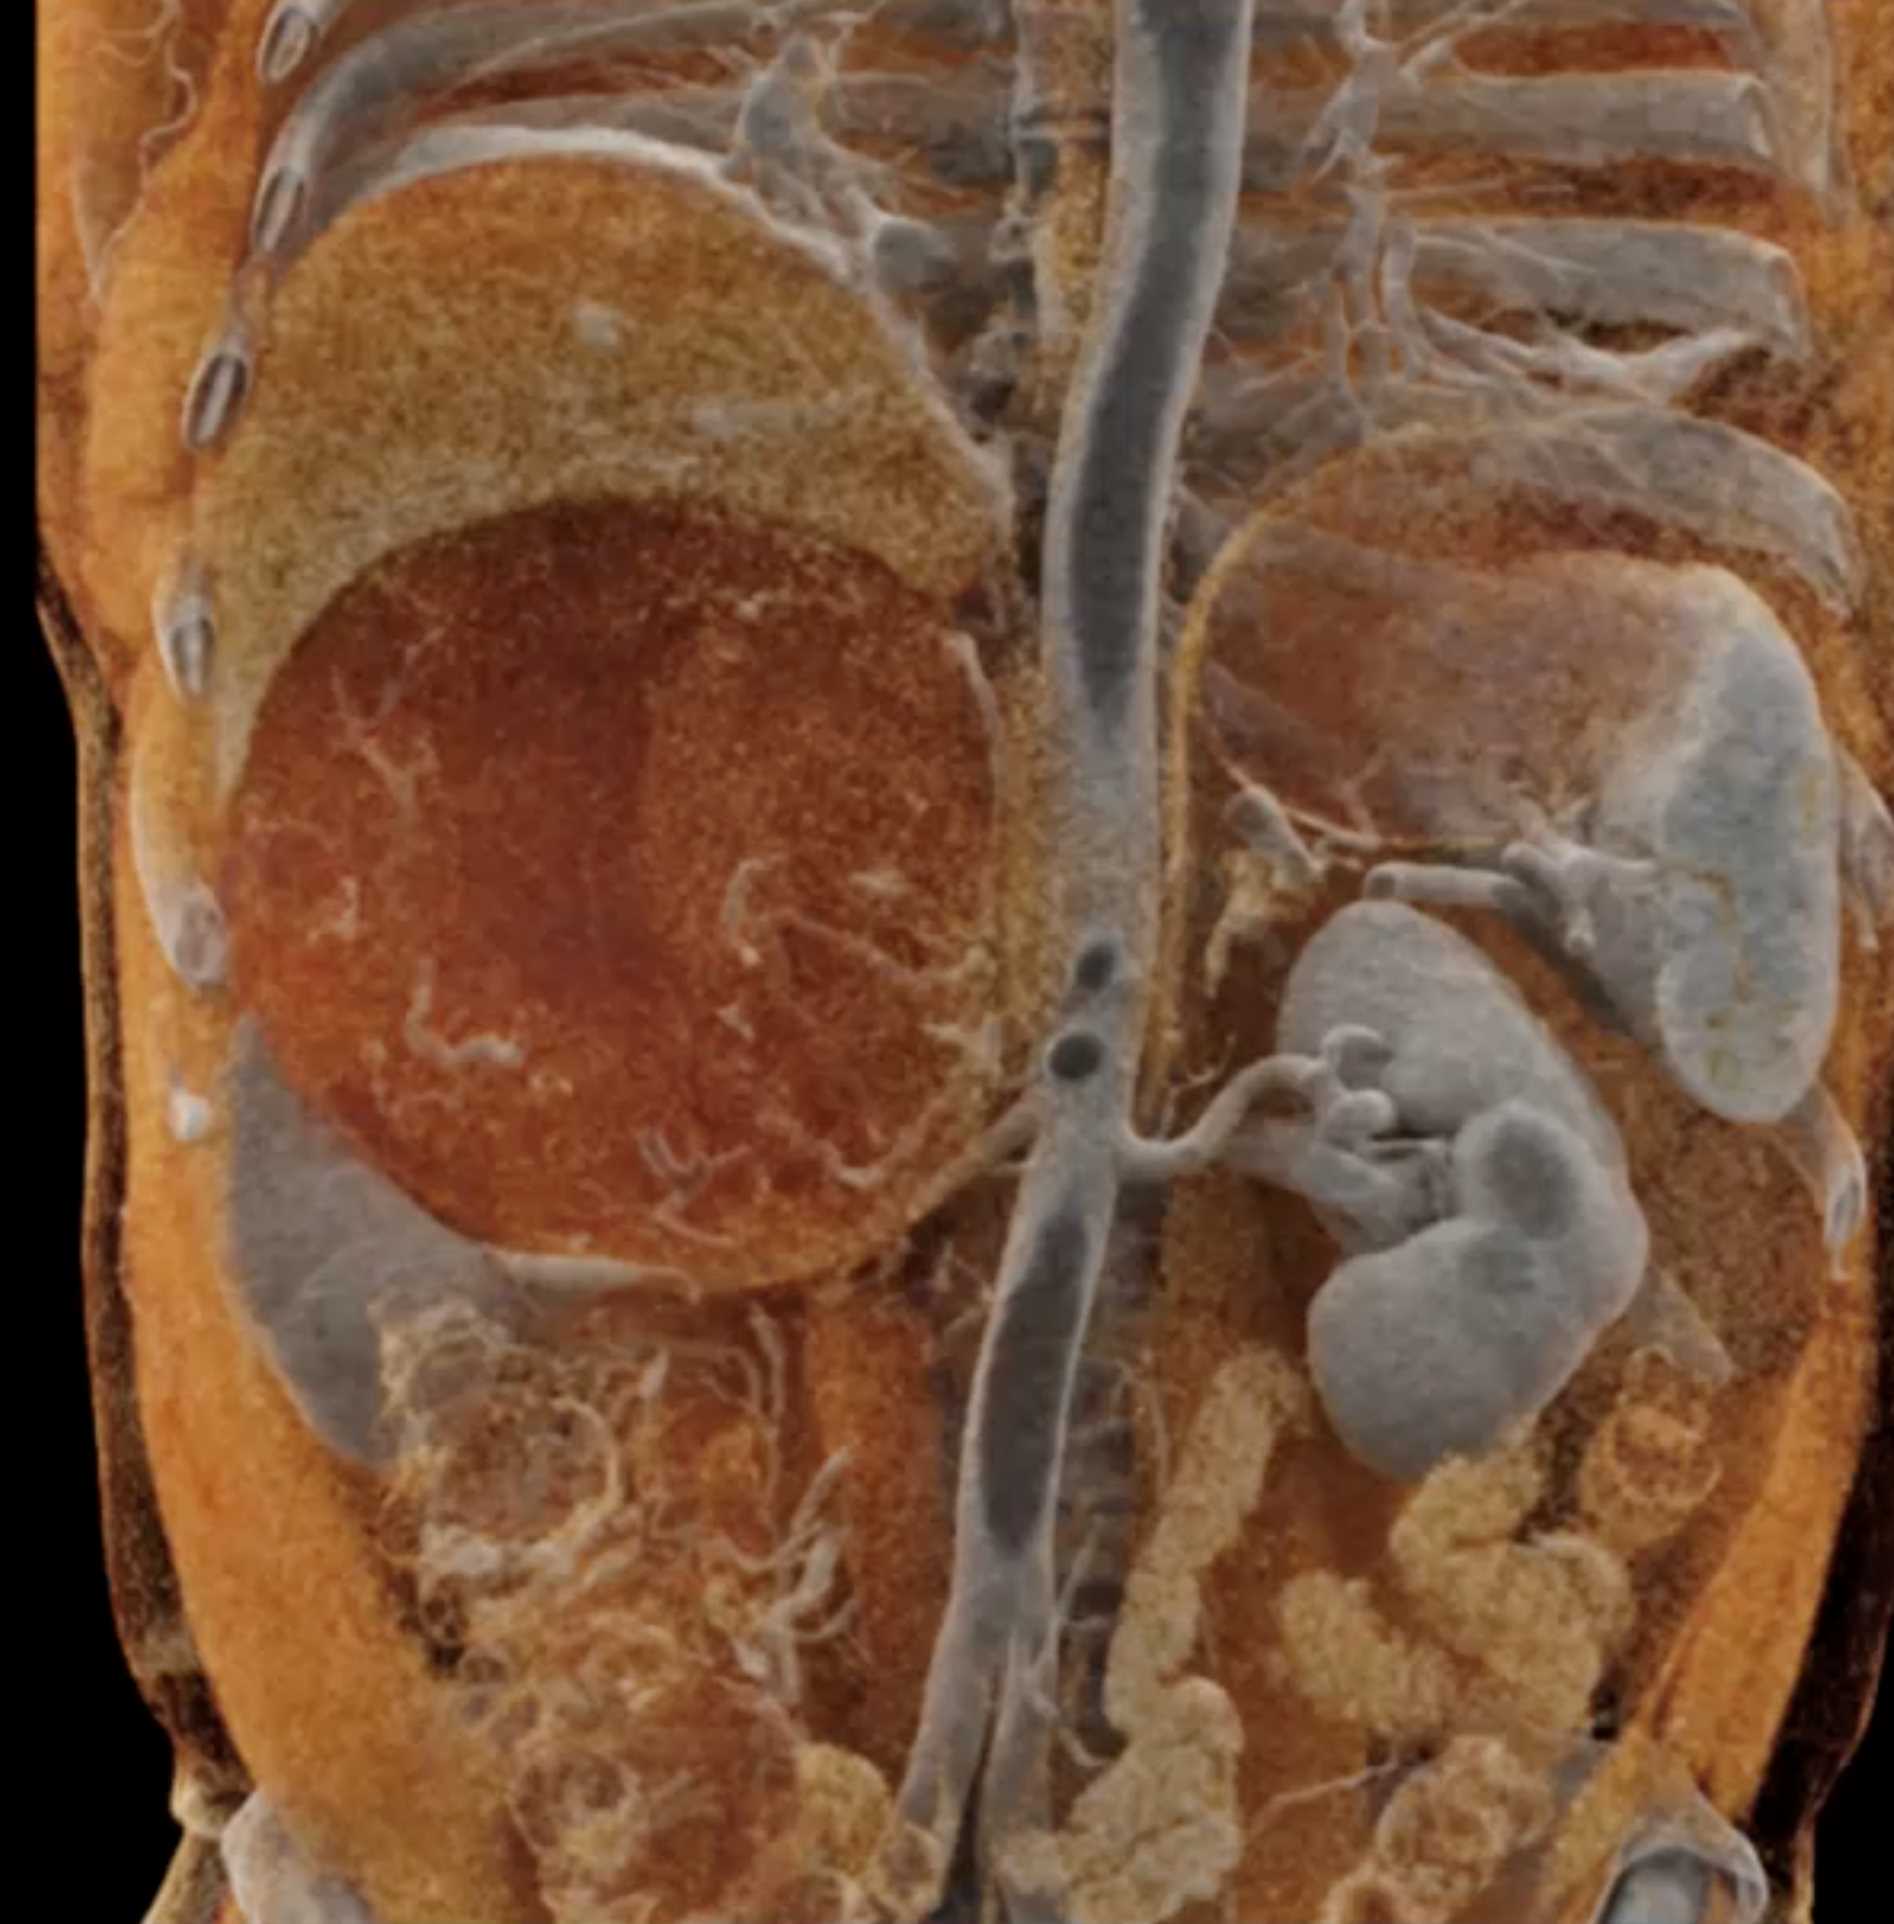

Left Adrenal Metastases from Renal Cell Carcinoma